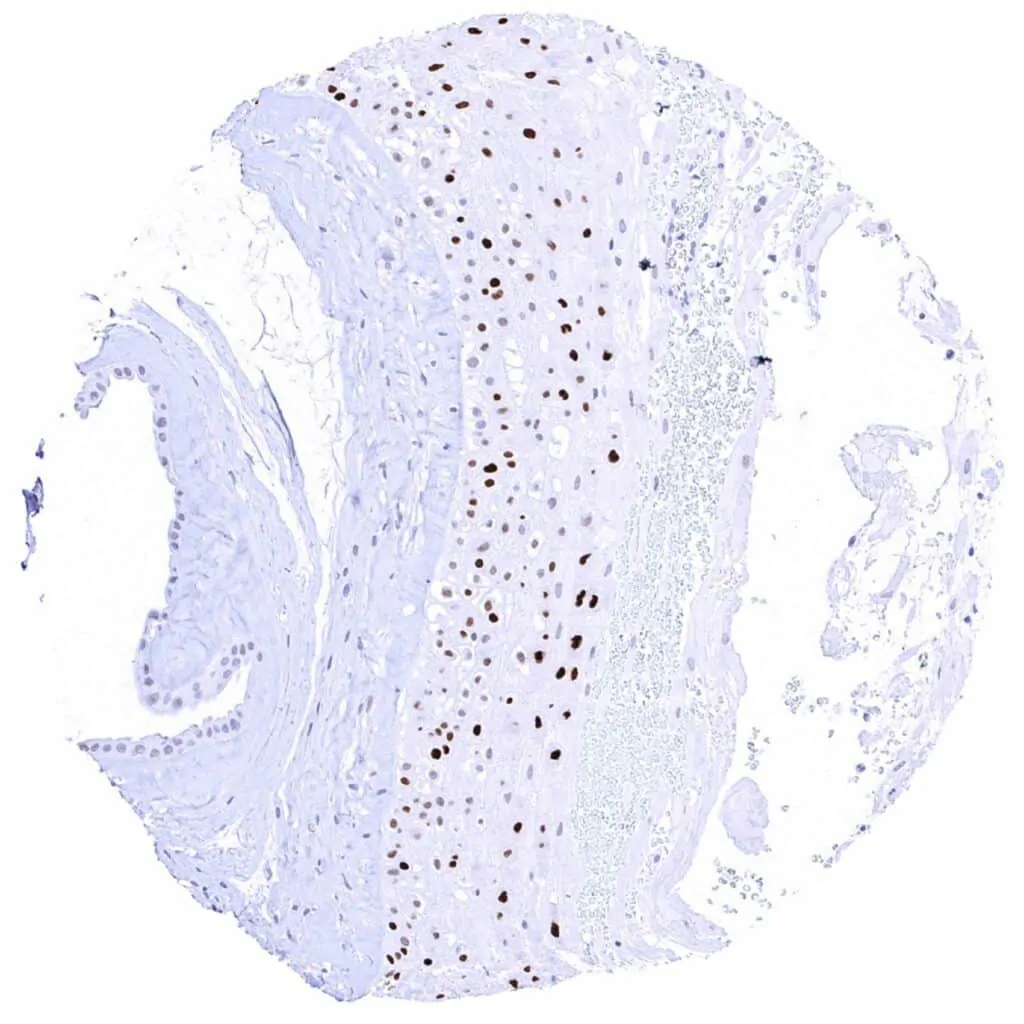

Esophagus, squamous epithelium Weak to strong nuclear Cyclin E1 staining of squamous epithelial cells in the upper half of the surface epithelium. The staining intensity gradually increases towards the surface